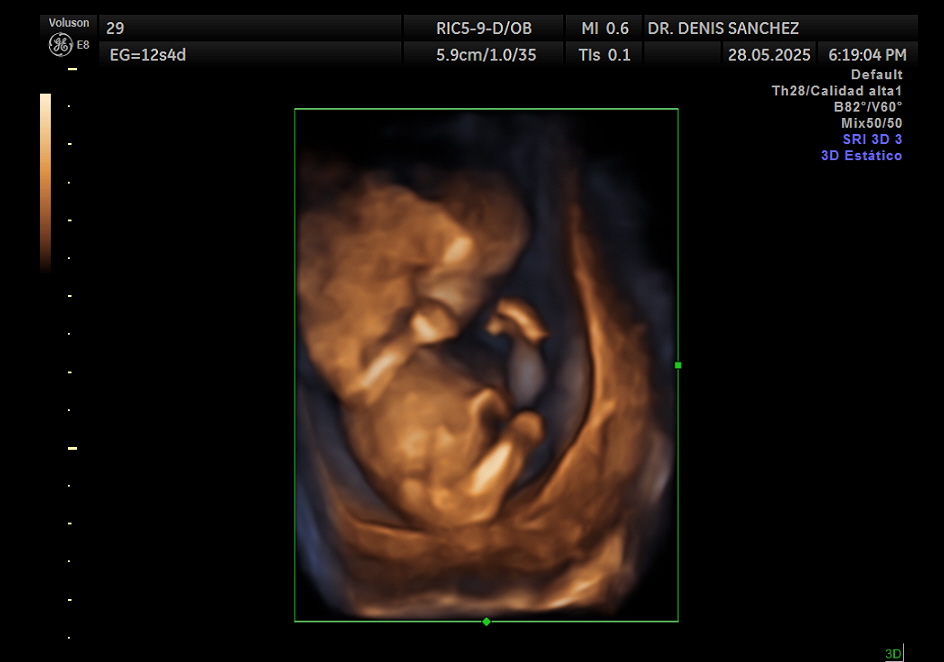

La ecografía cromosómica, también conocida como ecografía de tamizaje del primer trimestre, es una evaluación detallada que se realiza entre las 11 y 14 semanas de gestación. No analiza directamente los cromosomas, pero permite identificar marcadores ecográficos que podrían indicar un mayor riesgo de anomalías genéticas, como el síndrome de Down (trisomía 21), trisomía 18 o trisomía 13.

Determinar con exactitud la edad gestacional según la longitud céfalo-nalgas (CRL).

Este examen debe hacerse entre la semana 11 y 13 con 6 días, ya que es el período en el que los marcadores cromosómicos son evaluables con precisión. El momento ideal es cuando el bebé mide entre 45 y 84 mm de longitud céfalo-nalgas. Realizarlo fuera de este rango puede limitar la interpretación de los marcadores.

¿Qué se puede ver en una ecografía cromosómica?

Durante esta ecografía se observa:

Tamaño y forma general del bebé.

Frecuencia cardíaca fetal.

Marcadores de riesgo genético.

La anatomía básica del cráneo, columna, extremidades y órganos principales.

En muchos casos, una aproximación al sexo del bebé, aunque no sea definitiva.

Además, la ecografía puede detectar de forma temprana otras condiciones como hernias diafragmáticas, defectos de cierre del tubo neural o malformaciones mayores.